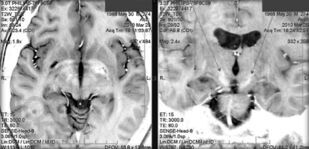

В монографии рассматриваются вопросы использования методов функциональной нейрохирургической коррекции в комплексной терапии больных с малокурабельными нервными и психическими расстройствами. Представлены исторические аспекты проблемы, нейрофизиологические основы стереотаксических нейрохирургических вмешательств, показания к операциям, методика отбора больных, виды и варианты современных методов функциональной нейрохирургии, а также результаты их применения при лечении отдельных нервных и психических заболеваний.